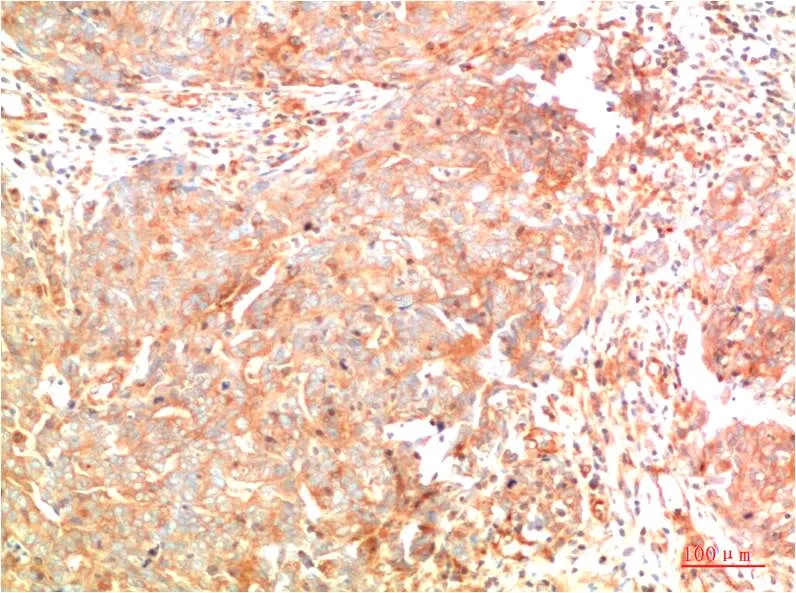

PTEN (7H2) Mouse Monoclonal Antibody

Cat: AMM00755

Size1:50μl Price1:$150

Size2:100μl Price2:$280

Size3:500μl Price3:$1200

Size2:100μl Price2:$280

Size3:500μl Price3:$1200